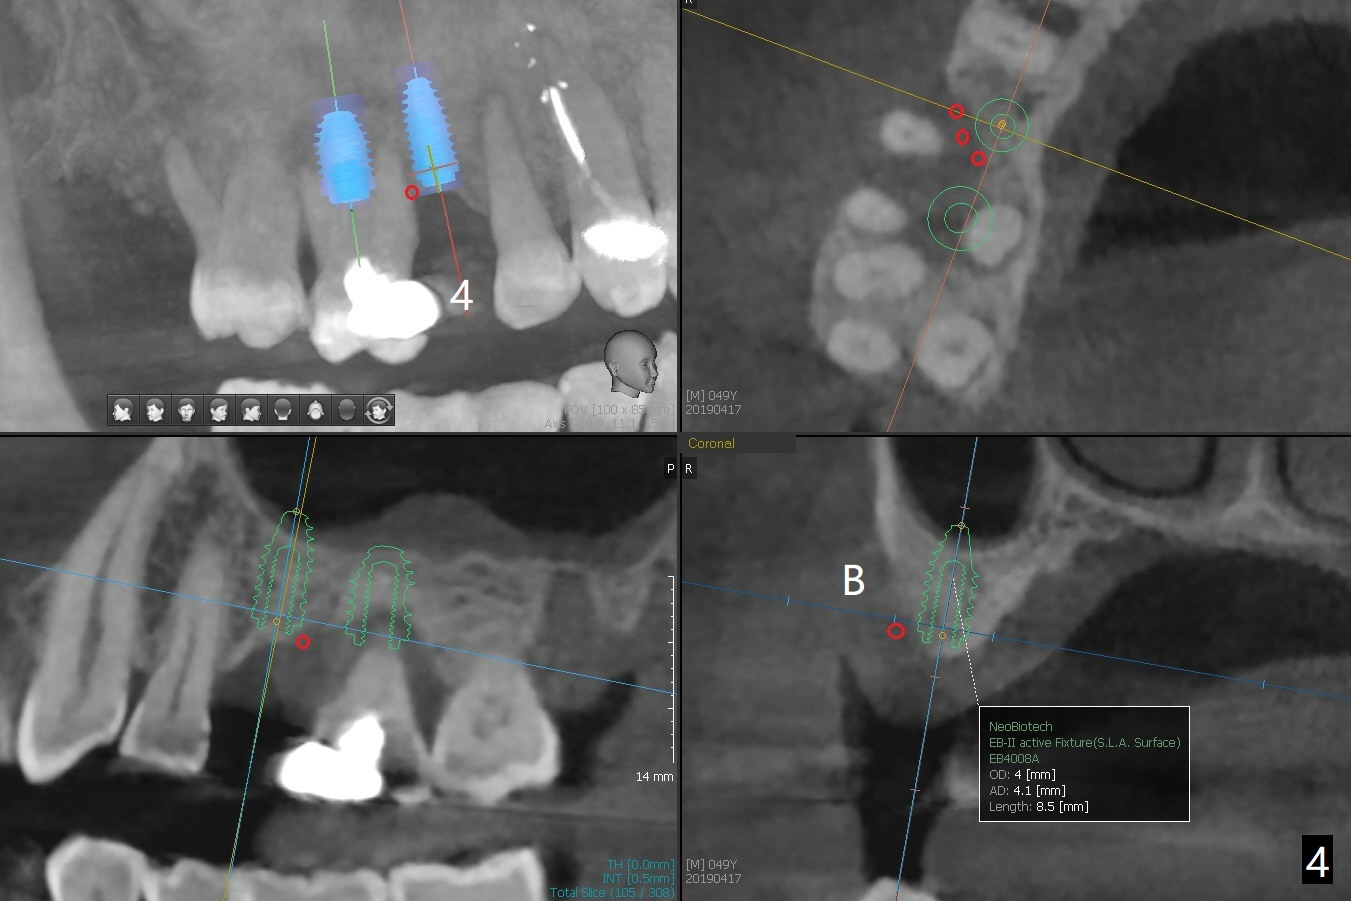

A 49-year-old man (patient of ours for 7 years) has severe bone loss and buccal recession at #3 with missing tooth at #4 (Fig.1,2,5). Short implants will be placed as palatal as possible (Fig.3,4 green) with buccal bone graft (red circles). PRF will be prepared for membranes and sticky bone.